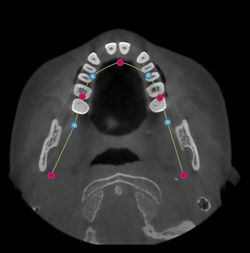

If the virtual template is not correctly distributed over the dental arch (extending evenly over the labial/buccal and lingual surfaces), edit its shape.

Change the shape of the blue line in the Edit Template wizard to make the curve coincide with the dental arch.

Click and drag the dots on the curve to change the position.

When the position of the blue line coincides better with the dental arch, click Finish.